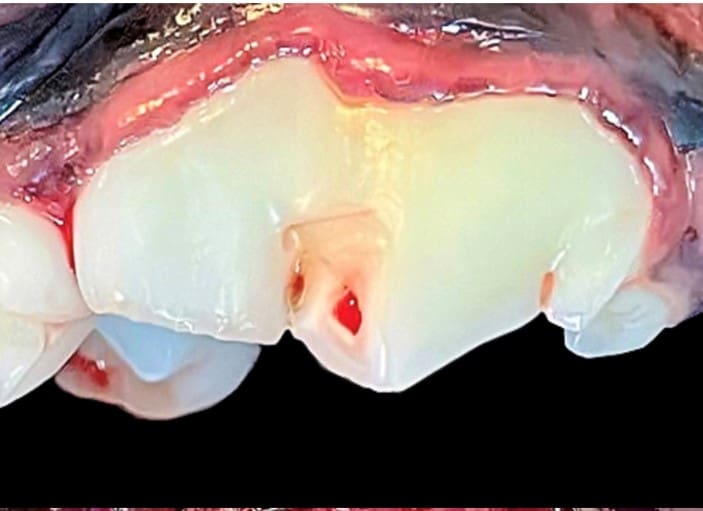

Yikes, My Dog (or Cat) Has a Broken Tooth!!